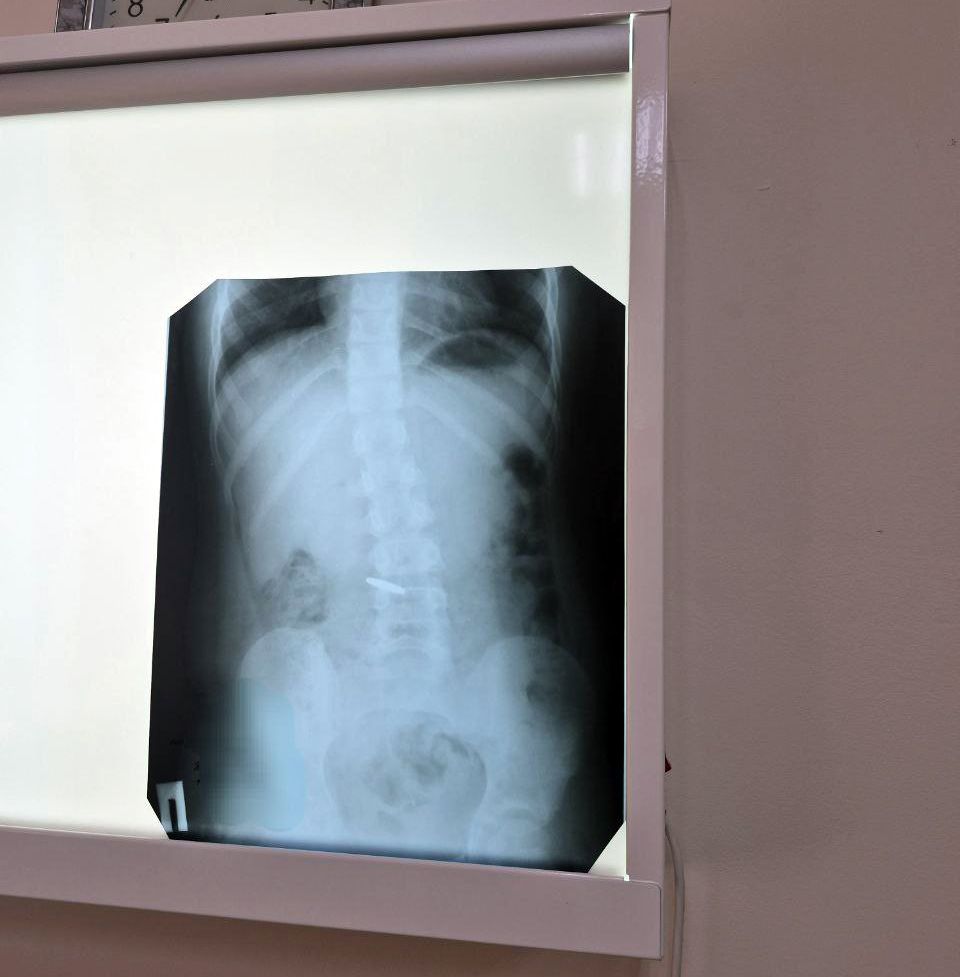

Также в субботу в больницу доставили ребенка, сбитого автомобилем во время катания на велосипеде, с множественными переломами ребер. Двое других юных пациентов проглотили инородные тела – монеты, одну из которых пришлось извлекать эндоскопическим путем. Завершили печальный список двое детей, госпитализированных с черепно-мозговыми травмами и переломами после ДТП.